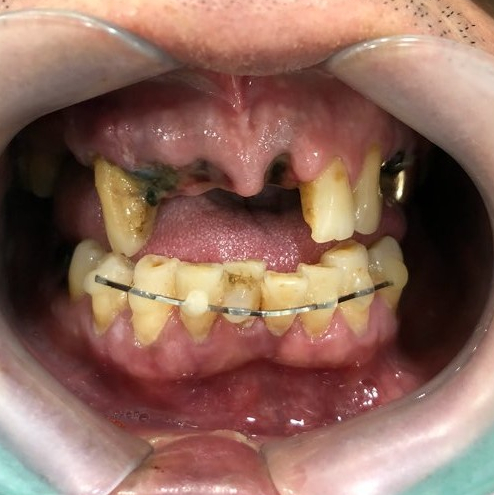

사고 직후 빠진 치아 (왼쪽 사진) -> 윗니 브릿지 및 아랫니 브릿지(오른쪽 사진)

환자분은 넘어졌다고 하셨나? 그랬지만 주변의 증언을 들으면 싸운 것 같다는...

이 환자분은 이미 치아도 빠지고 흔들리는 김에 치아 완전 고르게 해달라고 하셔서

흔들리는 이는 빠지고 치료해야 하는 치아는 처리해서 브릿지를 만들어 드렸고

환자분이 고르고 하얗게 된 이에 굉장히 만족 하셨습니다.